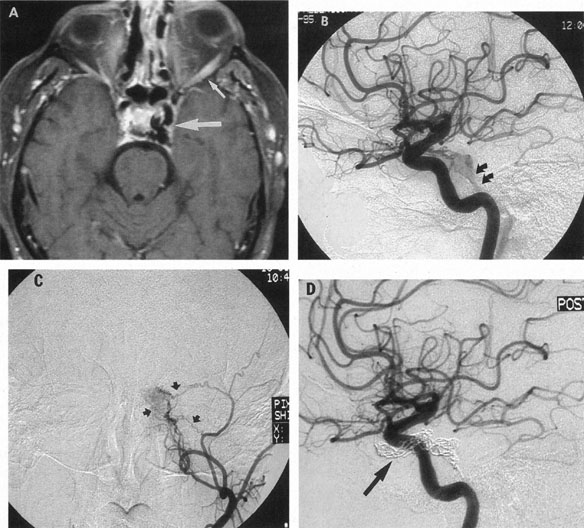

The detection of intracranial AVMs is facilitated by CT scanning and MRI (Fig. 10),88 but optimal management requires selective angiography89 that assesses the size and configuration of the mass, the number and location of feeding arteries, the flow characteristics and degree of steal from brain parenchyma, and the pattern of venous drainage.

Fig. 10. Neuroimaging of arteriovenous malformation. A: Coronal magnetic resonance imaging (MRI) (TR, 600 ms; TE, 20 ms) shows wedge-shaped vascular mass extending from the surface of the parietal cortex (white arrows) to the lateral ventricle (black arrows; asterisk, arterial feeder). B: Posteroanterior left arteriogram of the same lesion. C: Axial computed tomography scan with contrast enhancement. D: Axial MRI of a large arteriovenous malformation, first echo (TR, 2000 ms; TE, 20 ms). E: Second echo (TR, 2000 ms; TE, 90 ms). (From Smith HJ, Strother CM, Kikuchi Y, et al: MR imaging in the management of supratentorial intracranial AVMS. AJNR Am J Neuroradiol 9:225, 1988.)

The therapy for AVMs has been reviewed elsewhere.91–93 The preferred treatment remains complete surgical excision of the malformation. However, significant advances in endovascular and radiosurgical techniques have resulted in a marked increase in the use of multimodal, staged approaches to AVM treatment. A variety of intravascular techniques use embolization91 with materials such as particles of polyvinyl alcohol (PVA), platinum coils, and injection of liquid N-butyl-cyanoacrylate (NBCA) adhesive (Fig. 11). Complications of intravascular embolotherapy include vessel perforation by the catheter, migration of embolic materials, and infarction and hemorrhage of normal brain.

Fig. 11. Embolization of middle cerebral vessels that supply occipital lobe arteriovenous malformation (AVM). The patient had a subarachnoid and intraparenchymal hemorrhage that produced a left homonymous field defect. A: Right carotid arteriogram demonstrates contribution via posterior communicating artery to a right occipital lobe AVM. B: Vertebral injection. The arrow points to the enlarged right posterior cerebral artery that is a major feeder of the AVM. C: Right carotid arteriogram during glue embolization procedure. The arrow points to a catheter as it traverses the segment seen in (B). The catheter was advanced via the internal carotid artery but is positioned far posteriorly. D: Upper branches to the AVM now are occluded, with residual low-flow vascularization via the middle cerebral artery. E: Skull film showing radiopaque glue within the AVM and blood vessels previously supplying it. The patient had a persistent visual field defect but greatly reduced headache and no persistence of subjective bruit. (Courtesy of Dr. Joseph Horton.)